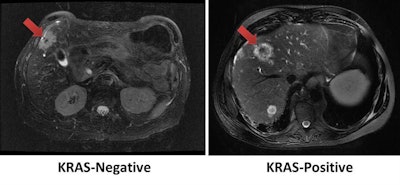

CHICAGO - Machine learning and quantitative MRI features can assist in predicting the KRAS mutation status of tumors in patients with metastatic colon cancer, according to research presented on Wednesday at the RSNA 2017 meeting.

Researchers from Harvard Medical School in Boston found that a machine-learning model that considers tumor radiomic features on MRI could yield a 95% accuracy rate for predicting KRAS mutation status -- a vital factor for determining patient prognosis and treatment decisions in metastatic colon cancer.

The Harvard researchers sought to assess the association between quantitative tumor MRI features and KRAS mutation status in patients with metastatic colon cancer. They also wanted to evaluate the role of machine learning-based radiomics in predicting tumor KRAS mutation status, Daye said.